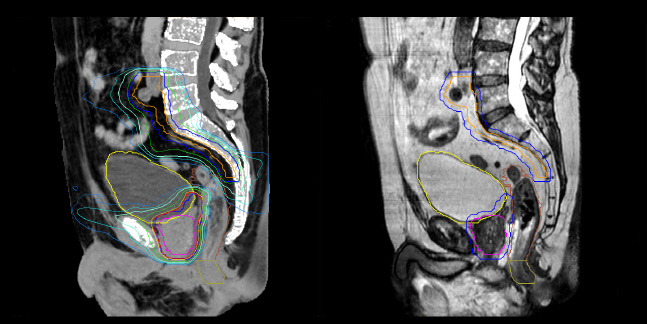

Evaluation of MRCAT dosimetric accuracy

Dosimetric equivalence validation was performed on 43 patient cases by comparing MRCAT-based dose plans overlaid on CBCT image dataset and on the corresponding MRCAT image dataset. Mr. Bolard and Dr. Champion found good agreement between MRCAT-based and CT-based dose calculations, with a mean dose ratio of 1.007 (0.991-1.014). The 3D gamma score was greater than 95% (95.2-99.0%) for all plans checked. A poster on this work was accepted for presentation at ESTRO 2020.

Dose plans overlaid on CBCT image dataset (left) and on MRCAT image dataset (right).

MRCAT is primary image dataset for dose calculation (left).

3D T2W TSE MRI with 36 cm Field-of-View is used for delineation of prostate and organs at risk (right).